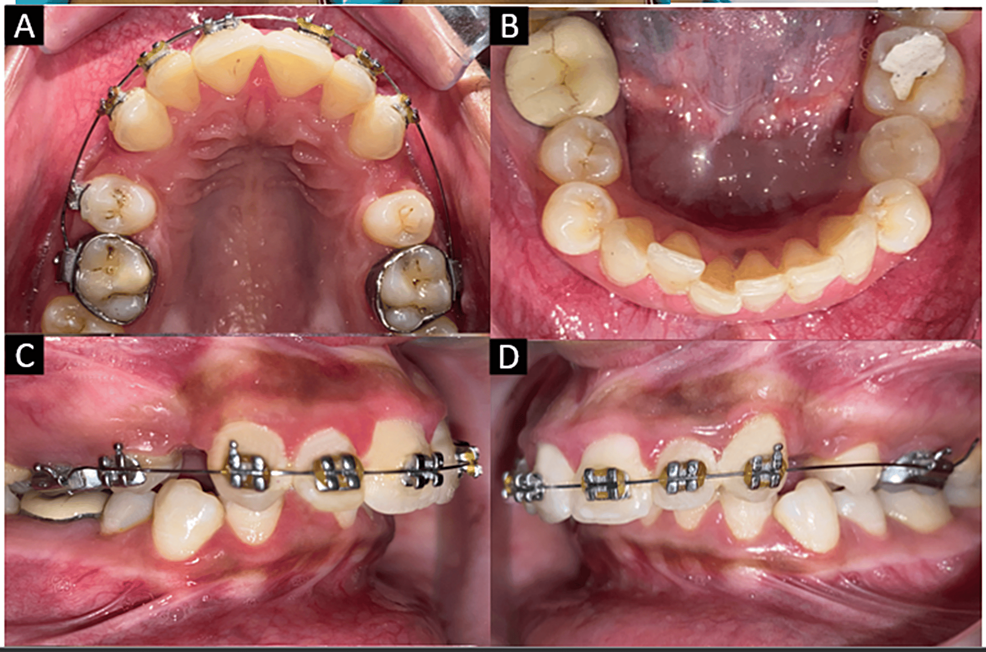

Intraoral picture and the illustration of the retraction of the Retraction Of Anterior Teeth Molar distalization has been a validated method to correct dental sagittal relationships and create space to relieve mild. The clinical objective is to prevent the mesial movement of the upper or lower molar teeth during retraction of the anterior teeth for. Though theoretically bone remodeling occurs during. Anchorage devices also known as tads is anterior teeth retraction, most commonly needed. Retraction Of Anterior Teeth.